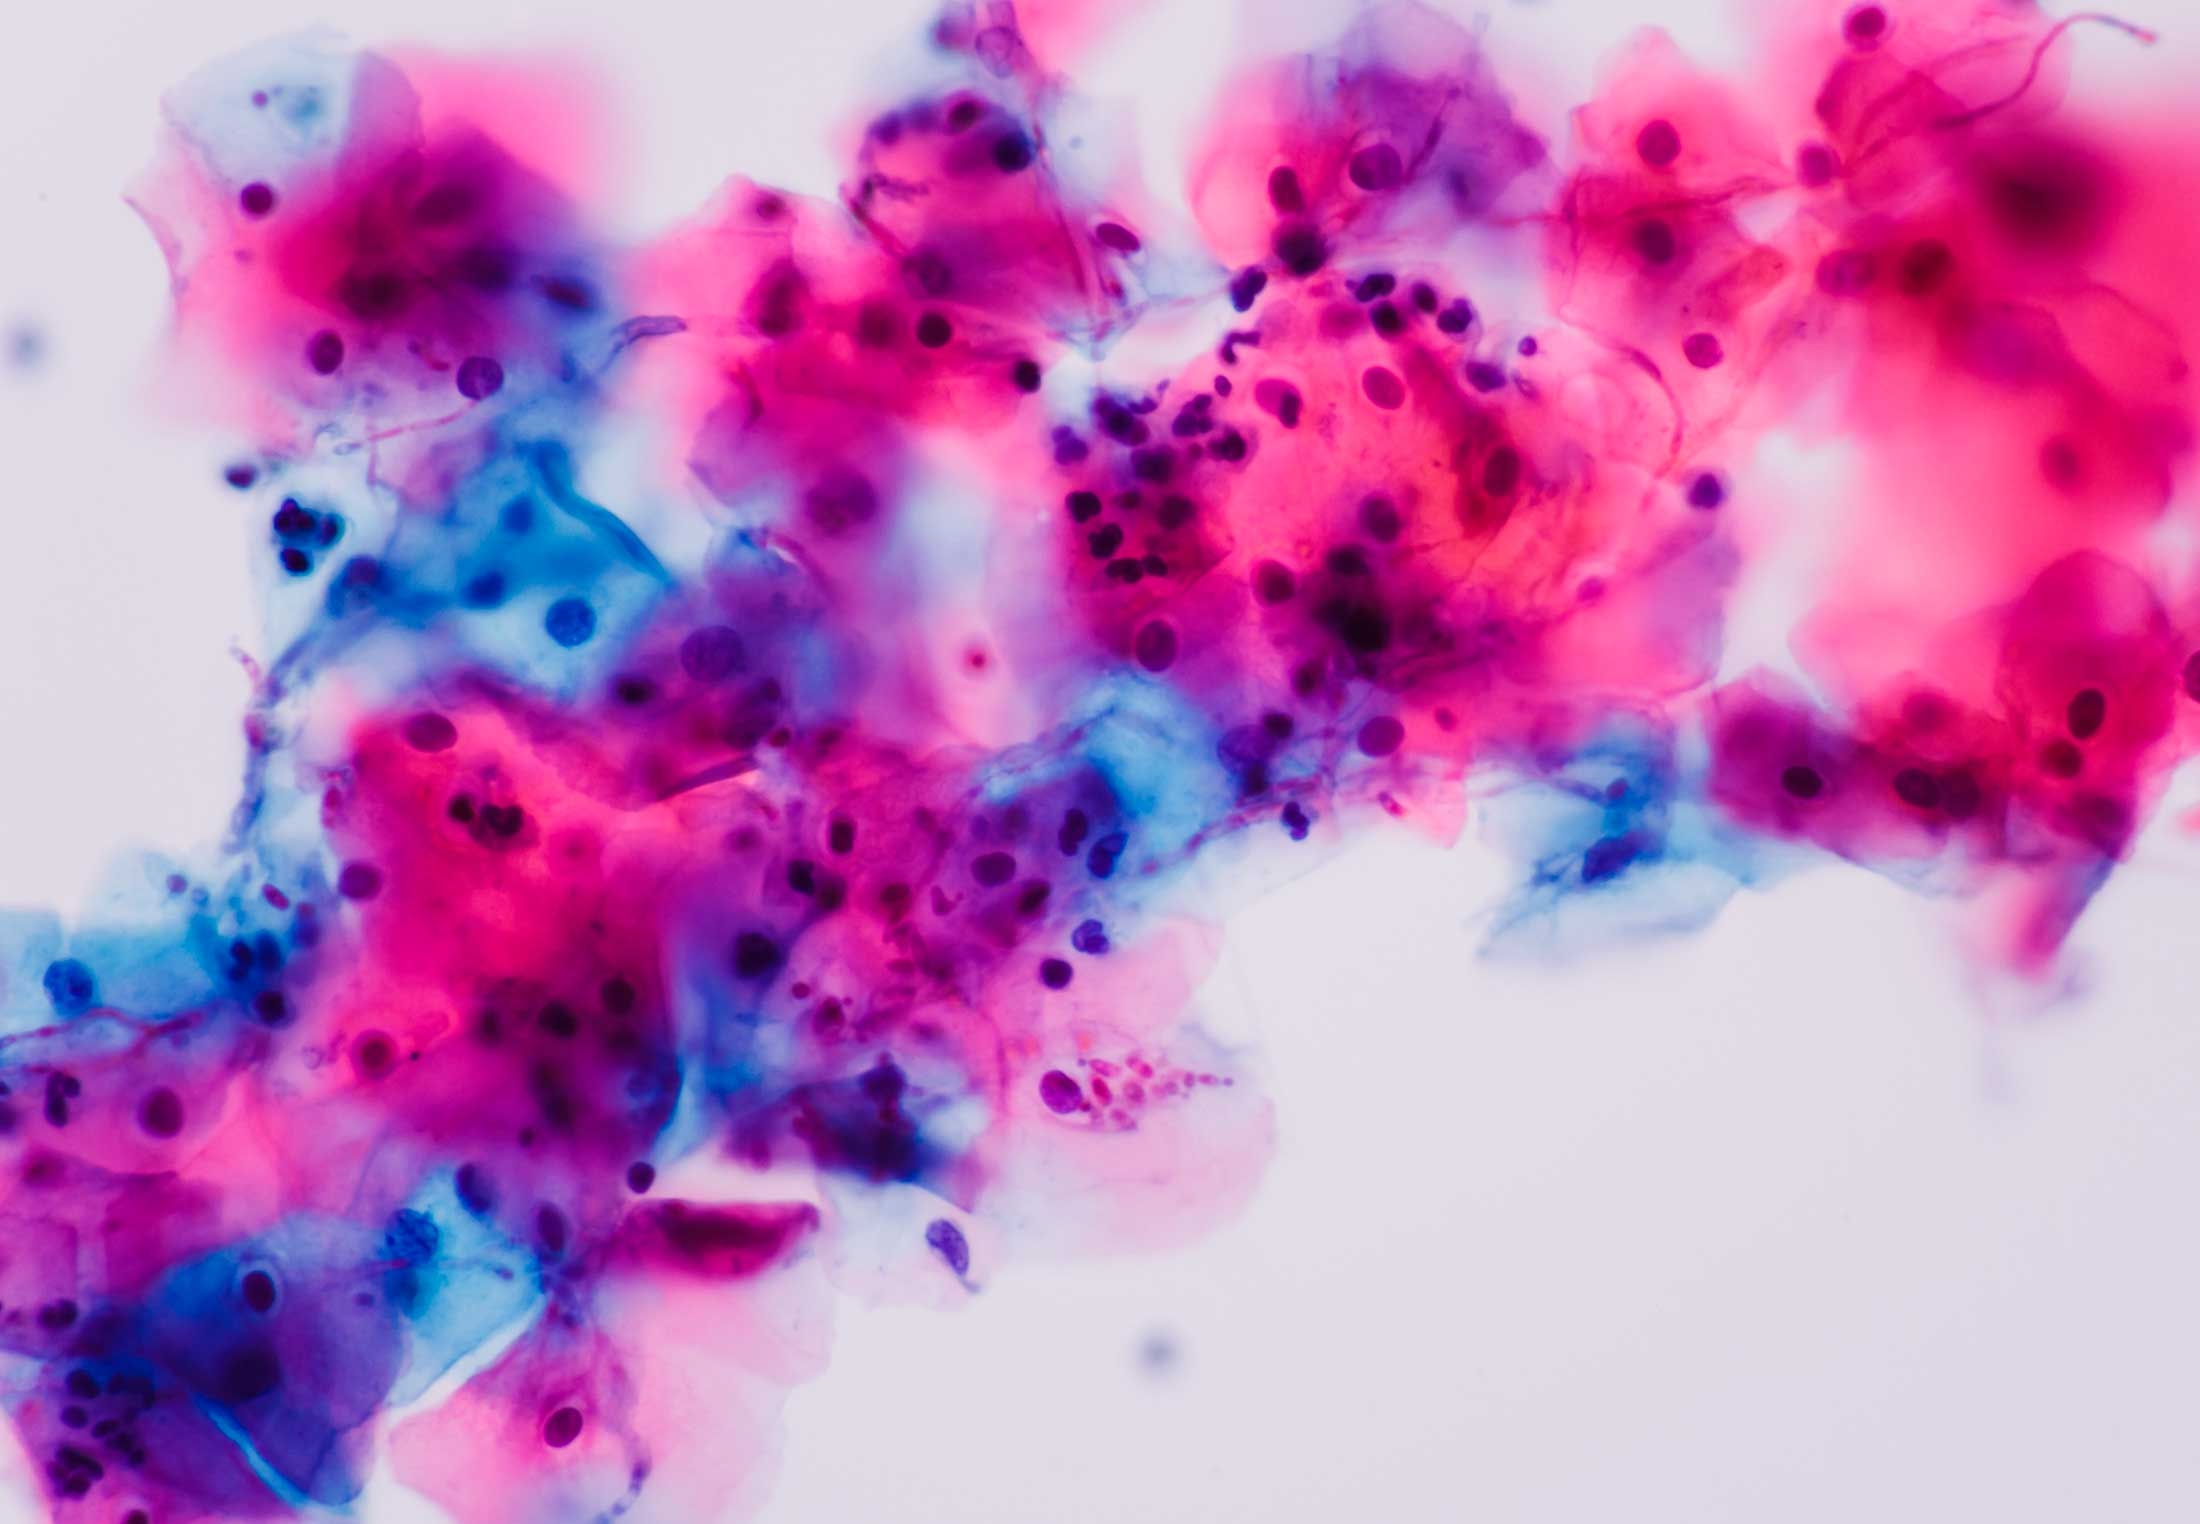

Кандида в мазке лечение

Кандида в мазке лечение 114 фотографий